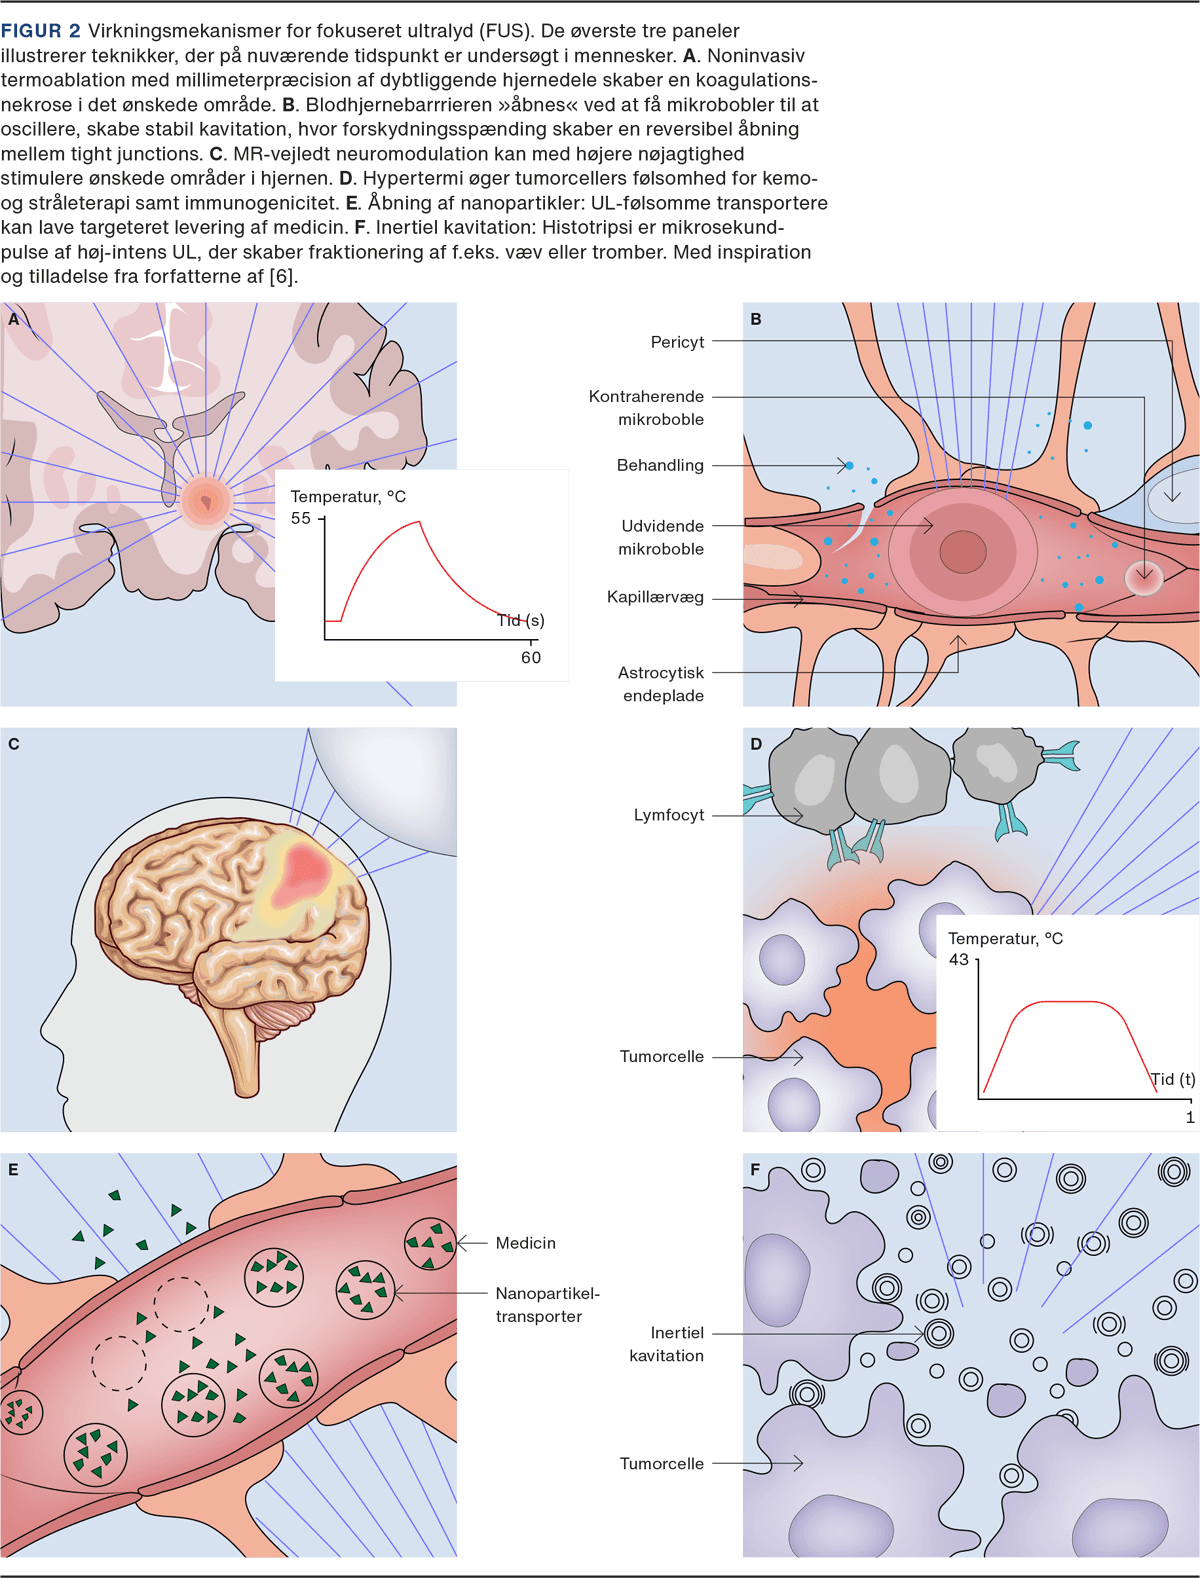

Der er udviklet en lang række eksperimentelle teknikker til FUS (Figur 2).

Termoablation

MRgFUS er aktuelt CE-mærket til behandling af essentiel tremor, tremordominant Parkinsons sygdom samt kroniske smerter. Termoablation af hjernevæv har været forsøgt hos primær hjernetumor-patienter i flere kliniske forsøg, men det samlede antal af patienter, der har modtaget behandling af denne type, er fortsat ganske begrænset [15]. Initialt var det teknisk nødvendigt at foretage en kraniektomi og implantere en transducer for at forhindre distortion af UL-bølgerne, men teknikken er blevet udviklet, så den kan anvendes noninvasivt [16]. Proceduren ved MRgFUS ved benigne og maligne tilstande er den samme og beror på høj-intens FUS. Det er et håb, at MRgFUS på sigt kan blive et ekstra behandlingstilbud til patienter med hjernetumorer, hvor der tidligere er givet maksimal strålebehandling, og hvor der i øvrigt ikke er mulighed for kirurgi.

Begrænsninger i teknologien bag FUS gør fortsat, at de ønskede læsioner skal befinde sig relativt centralt i hjernen, da passagen gennem kranieknoglen således er kortest, med minimal opvarmning af knoglevævet som komplikation [17].

Derudover er størrelsen af det område, det er muligt at behandle, fortsat ganske begrænset – dette er en udfordring, idet hjernetumorers diffuse vækstmønster gør, at det nødvendige behandlingsområde ofte er stort.

Åbning af blod-hjerne-barrieren

En af de mere velundersøgte teknikker ved FUS omhandler åbning af BBB (BBBO) [18]. Den kontrollerede, reversible og sikre åbning af BBB beror på en kombination af lav-intens MRgFUS kombineret med injektion af såkaldte mikrobobler (f.eks. UL-kontrastmidler), der gør, at UL-effekten fokuseres på kapillærniveau. Den præcise virkningsmekanisme er ukendt, men menes at tage udgangspunkt i »stabil kavitation«, hvor mikroboblerne oscillerer fra minimal til maksimalt stabilt volumen, hvorved karvæggen og dermed BBB udsættes for forskydningsspænding. På denne måde brydes tight junctions mellem endotelcellerne, og der skabes en forbigående spatiel afgrænset BBBO [19]. Ved højere frekvenser risikeres det, at boblerne brister – den afsatte kraft i karvæggen bliver derved så stor, at selve karvæggen og ikke kun BBB beskadiges. Teknikken minder om en operasanger, der kan ramme den præcise tone og derved få et vinglas til at vibrere og sidenhen ødelægges.

Integriteten af BBB har vist sig at genetableres inden for 6-24 timer. Der er dermed tid til, at de ønskede kemoterapeutika kan nå at passere BBB. Med FUS BBBO har man været i stand til at få dekstranmolekyler (2.000 kDa) til at passere BBB [20], ligesom det har været muligt at skabe transport af forskellige kemoterapeutika, virale vektorer og stam- og immunceller [21]. Selve åbningen af BBB kan valideres med MR med kontrast (Figur 3).

Temperaturstigningen i vævet ved teknikken er minimal, og effekten, der skal bruges ved BBBO, er under tre gange mindre end ved termoablation af hjernevæv [23].

Hypertermisk terapi, hvor temperaturen af vævet øges med højintensitets-MRgFUS til 40-45 ˚C, øger immunogeniciteten, radioterapi- og kemoterapifølsomheden. Teknikken er primært undersøgt til systemisk kræftsygdom, men i et enkelt ældre studie har teknikken været forsøgt anvendt mhp. behandling af GBM [28].

Sonodynamisk terapi, hvor UL-følsomme molekyler, der ophobes i tumorvæv (f.eks. 5-aminolevulinsyre) og vha. en endnu ukendt virkningsmekanisme »aktiveres« med FUS. Derved skabes frie reaktive radikaler, som ultimativt fører til apoptose af tumorcellerne [29].

Histotripsi, som beskriver høj-energi FUS, der afgives i mikrosekundpulse og fraktionerer væv mhp. ikketermoafhængig ablation af tumorvæv eller destruktion af tromber. Teknikken er kendt i urologien, hvor litotripsi er en lignende UL-teknik til transkorporal fjernelse af sten i urinvejene. Teknikken er fortsat eksperimentel [30].